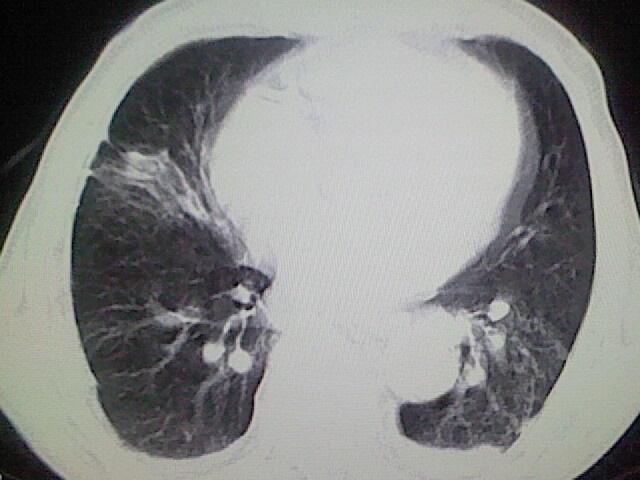

以下是引用zsl6918在2008-8-28 16:49:00的发言:[br]双肺炎性病灶,食管狭窄估计与心房增大压迫所致。

以下是引用xulianj在2008-8-28 20:36:00的发言:[br]慢支肺气肿伴感染,右上肺陈旧性结核;食道建议胃镜检查。

以下是引用wqs571018在2008-8-28 21:18:00的发言:[br]慢支继发感染,右上肺陈旧性结核;食道建议胃镜检查。